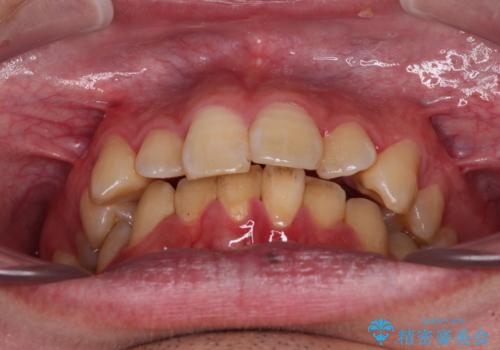

上顎前歯のデコボコを改善してスッキリした口元に ワイヤー装置での非抜歯矯正

- 上顎前歯のデコボコを気にして来院された患者様です。

上下前歯にデコボコがありましたが、特に上顎の叢生が強く、通常に歯列を整えると、上顎が前方に突出し、口元の突出感が残った仕上がりとなる可能性が考えられました。

補助装置を用いて上顎歯列全体を後方に移動させる力をかけ、唇が閉じやすいような仕上がりを目指して、ワイヤー装置にて矯正治療を行うこととしました。